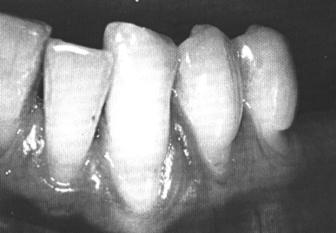

У женщин эмаль зубов состоит из вертикальных полос. Встречаются случаи, когда эмаль имеет тусклый цвет и на ней видны участки белой эмали.

на коронках зубов имеются вертикальные полосы с почти нормальной толщиной эмали, чередующиеся с полосами ее гипоплазии.